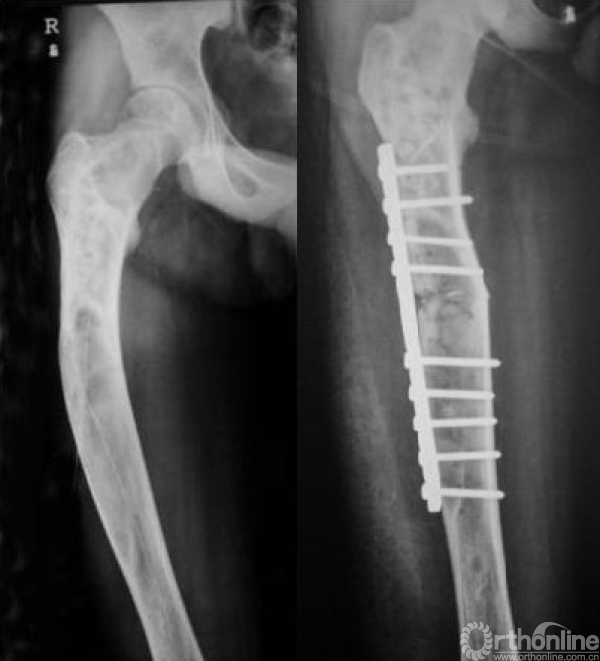

手术治疗:

一般以为,无症状的多发骨纤不需要手术治疗,主要是观察和预防病理性骨折和畸形的发生,如发生骨折通过适当的外固定可愈合。成人单发性病变,明显影响骨的机械支持力,特别是下肢、并造成一定畸形的病人可选择手术治疗(图10)。对于病变范围大合并病理骨折、濒临骨折或畸形较重的多发骨纤,可直接使用髓内针固定,而不需要处理病变本身

图10 截骨矫形术